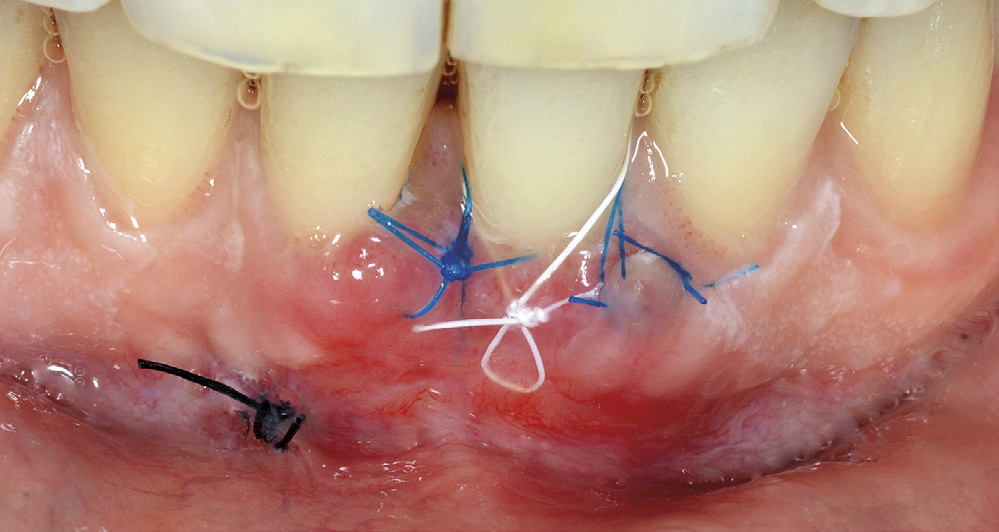

Ein kirurgisk korreksjon med bruk av «konvolutt-teknikk» og ganetransplantat vart tilrådd som behandling for å dekka den labiale retraksjonen 31. Dette behandlingsalternativet vart diskutert med pasienten og ho samtykte. Etter å ha planert rotoverflata på 31, vart marginalt vev mobilisert og lomma utvida apikalt og lateralt utan vertikale hjelpesnitt (figur 5 A). Det vart så lagt eit horisontalt snitt tilsvarande breidda på transplantatet langs palatinale tannrekke regio 24, 25 og deretter to vertikale snitt mot midten av ganen med ei lengde som svara til høgda på transplantatet. (figur 5 B). Det underliggjande bindevevslaget vart fridissekert og transplantatet plassert i blautvevslomma labialt på 31 slik at heile retraksjonen vart dekka (figur 6). Transplantatet vart så stabilisert med ikkje-resorberbare suturar. Ganeepitelet vart replassert og primær sårlukking sikra med enkle suturar. Suturane vart fjerna 13 dagar postoperativt.

Kontroll etter 7 dagar viste rolege kliniske tilhøve med full dekning av retraksjonen til emalje-sement-grensa (figur 7). Raud gingiva labialt er teikn på god blodforsyning og aktiv sårtilheling i operasjonsområdet. Pasienten hadde mista ein sutur i ganen. Aktive suturar vart fjerna 6 dagar seinare. Postoperativ kontroll etter 4 månader viser optimal sårtilheling og full dekning til emalje-sement-grensa (figur 8). Eittårs kontroll viser stabile gingivale tilhøve med ei brei og kraftig sone med keratinisert gingiva labialt 31. Det er framleis full dekning (100%) av den opphavlege gingivale retraksjonen og ingen sonderbare lommer (figur 9).

Figur 6. Transplantat plassert og suturert i lomma.